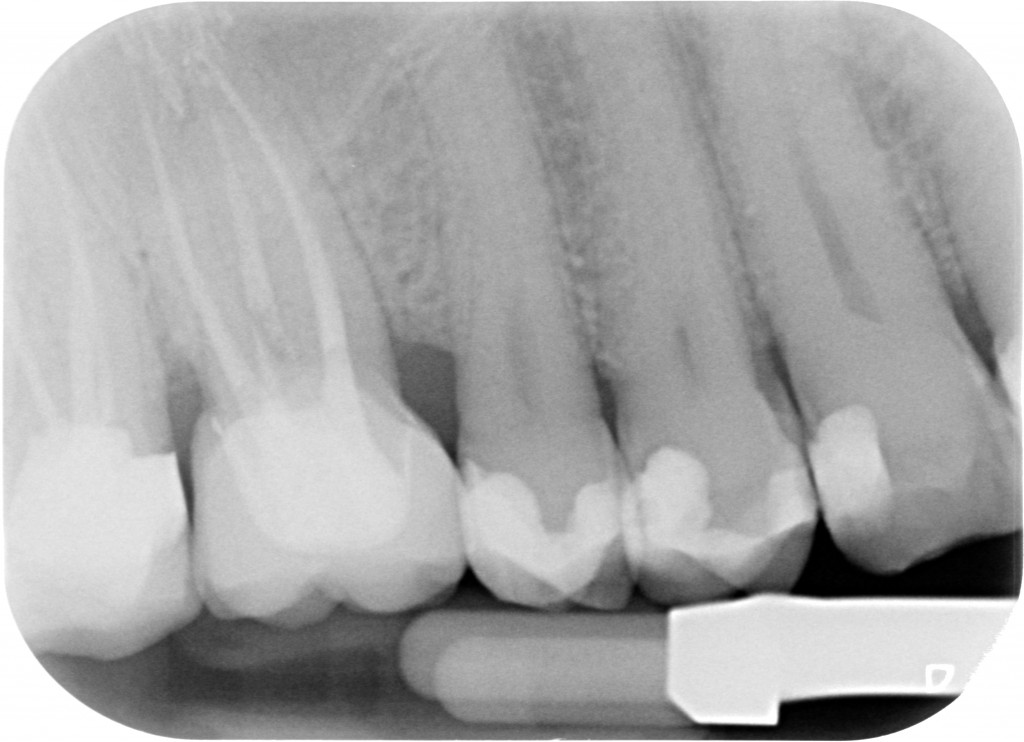

Il riposizionamento apicale dei tessuti parodontali ci consentirà quindi di:

ESEGUIRE UN CORRETTO PRETRATTAMENTO CORONALE

ESEGUIRE UN CORRETTO RITRATTAMENTO CANALARE ISOLANDO IL CAMPO CON LA DIGA DI GOMMA

ESEGURE UN CORRETTO RESTAURO PROTESICO